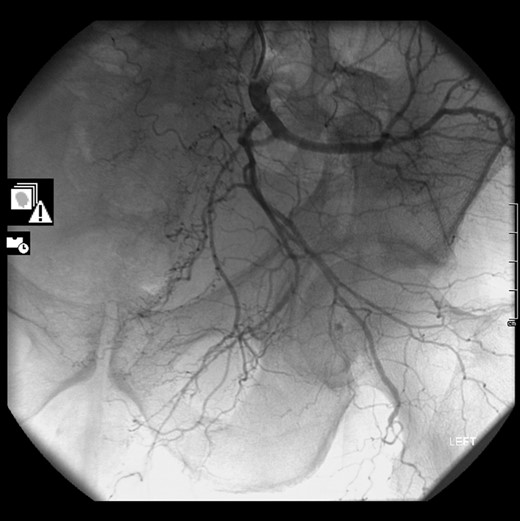

The following morning, he was taken to the radiology suite where he underwent CT Angiogram which demonstrated no arterial bleed. After discussion with the vascular team and further review of his images, the patient was recommended for prophylactic embolization. Almost 48 h after admission, he had gelfoam embolization of anterior and posterior division segmental branches of the left internal iliac artery. After consultation with the regional pelvic surgeon, a 10 lb skeletal traction was applied to take pressure off the acetabulum. Following 5 days in the intensive care unit, he was discharged to the orthopaedic ward. Further complications arose due to his coagulopathic state. He developed uncontrollable bleeding from his pin site while in skeletal traction, which needed removal and continuous pressure applied to the wound. He died on 30 January 2017, 51 days after admission, as a result of his chronic liver disease.